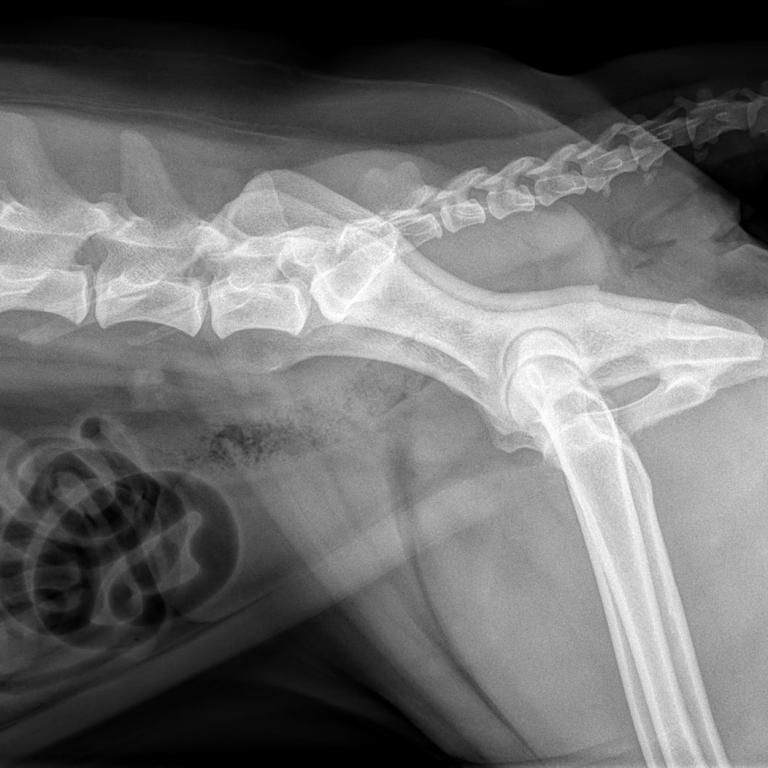

Eine leistungsstarke Röntgenanlage, ein modernes High-End-Ultraschallsystem und ein Videoendoskop ermöglichen uns ein breites Spektrum an bildgebender Diagnostik.